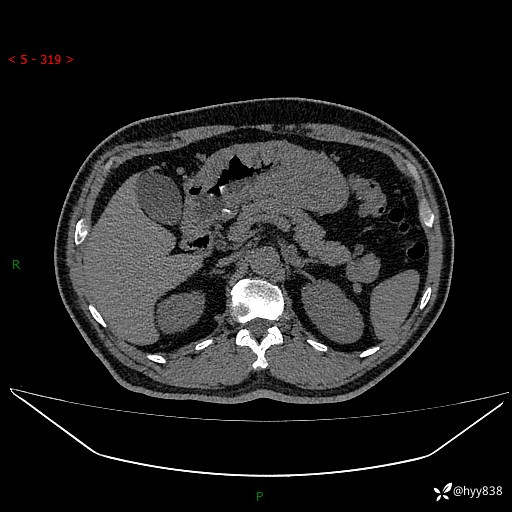

胰腺CT平扫